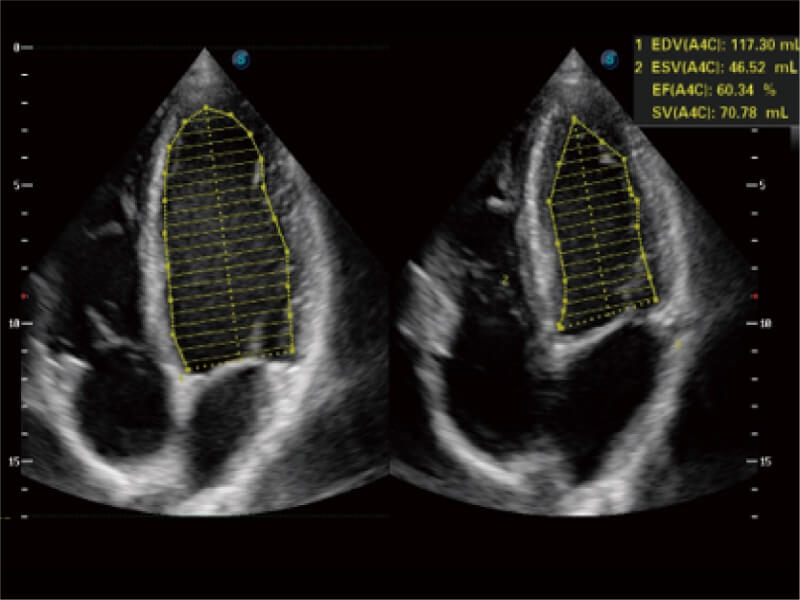

能夠基于左心室壁追蹤和辛普森法,自動(dòng)計(jì)算射血分?jǐn)?shù),支持多個(gè)可移動(dòng)點(diǎn)描跡,與手動(dòng)測(cè)量相比,極大節(jié)省了動(dòng)物醫(yī)生的時(shí)間和精力。

ProPet 80 配備了豐富的心臟探頭群、先進(jìn)的成像技術(shù)和專業(yè)的心臟測(cè)量工具,可幫助動(dòng)物醫(yī)生為不同體型和生理結(jié)構(gòu)的動(dòng)物提供心臟和心肌功能的全面評(píng)估。